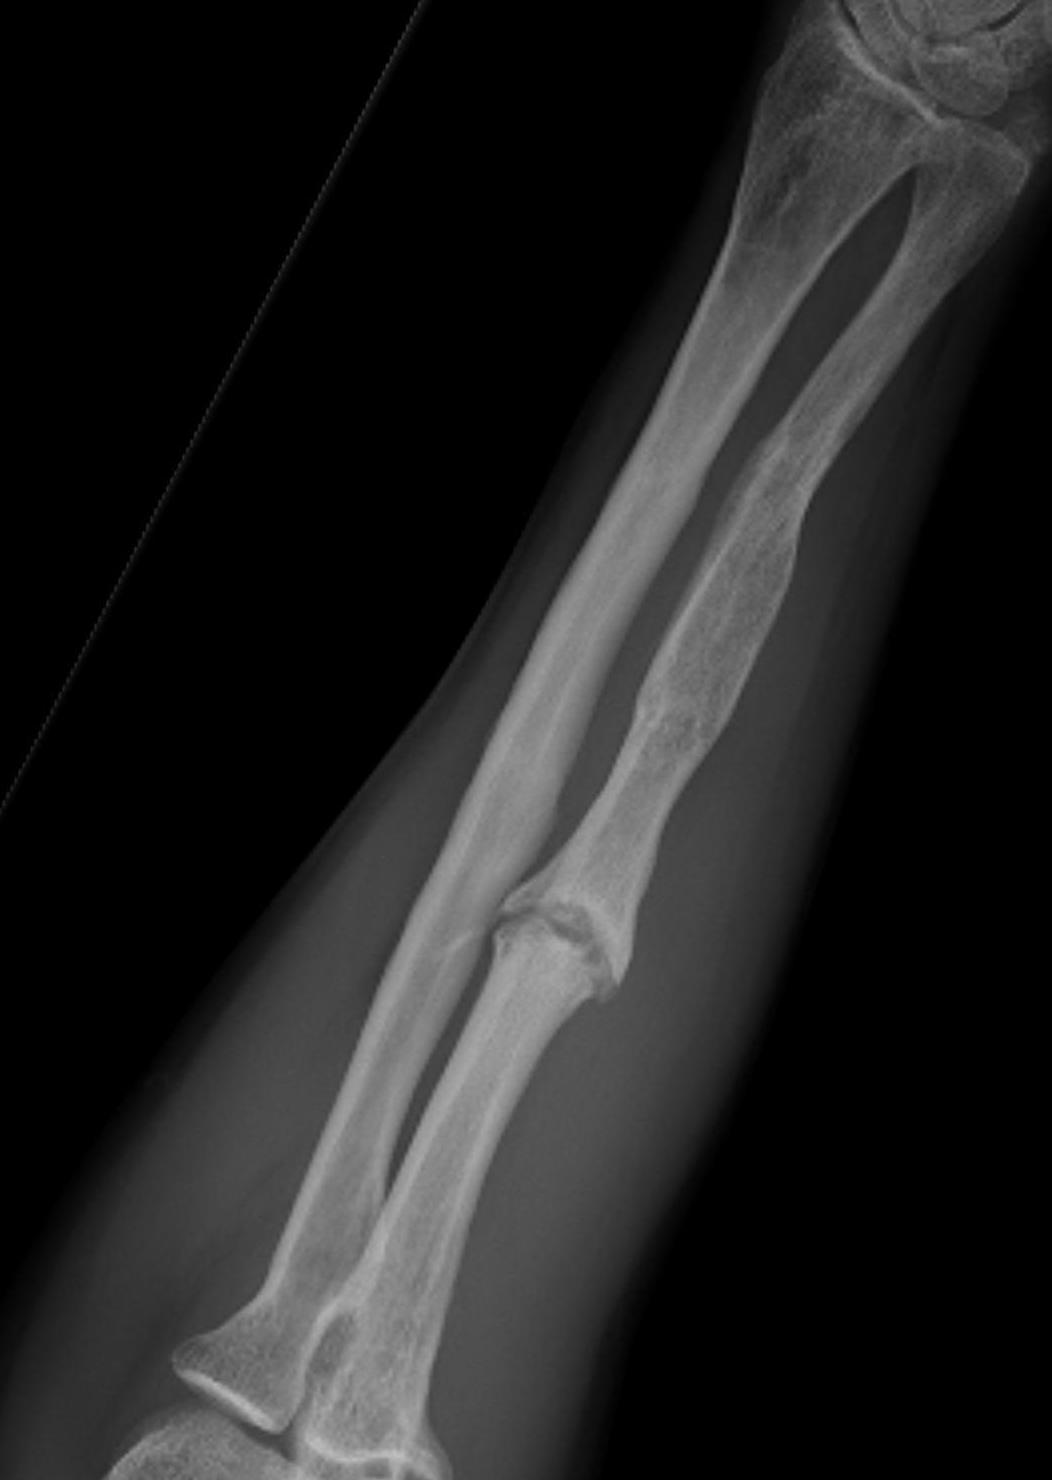

Midshaft / middle 1/3

Increased nonunion rates with midshaft versus distal fractures

- increased nonunion with midshaft (30%) versus distal 1/3 fractures (2%)

- midshaft ulna fractures - higher risk of nonunion